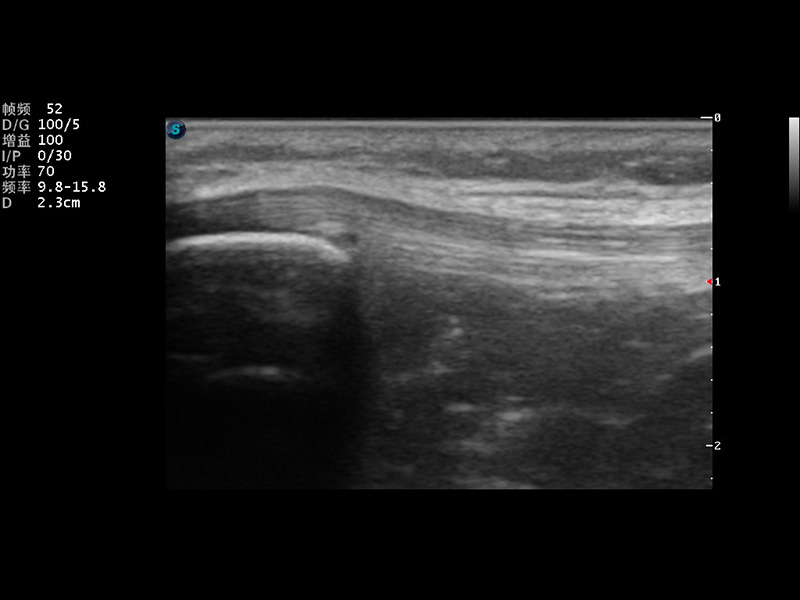

S9便携式彩色多普勒超声诊断仪是竞技宝(JJB)官方网站研发的高端便携彩超设备,外观设计新颖、产品性能卓越。S9在便携超声领域采用了突破传统的触摸屏交互设计,并以先进的软件硬件技术和设计理念,为您带来清晰的图像质量、稳定的工作性能和便捷的操作体验。